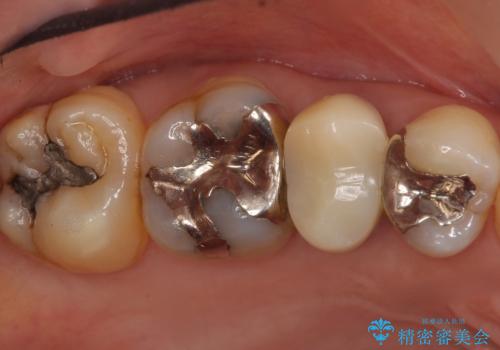

欠けている奥歯(左上5)は失活歯で、保険内の銀の詰め物(メタルアンレー)で治療されていました。

金属の詰め物と土台を除去し、ファイバーコア(金属を使わない強くてしなやかな土台)を植立したのちセラミッククラウンによる補綴治療を行いました。

精査したところ、右上の奥歯(右上5)に根尖病変を認めたため、こちらは根管治療後にセラミッククラウンによる補綴を行いました。

- ¥407,000 (根管治療×1本、土台×2本、仮歯×2本、クラウン×2本) ※税込費用は治療当時の料金となります